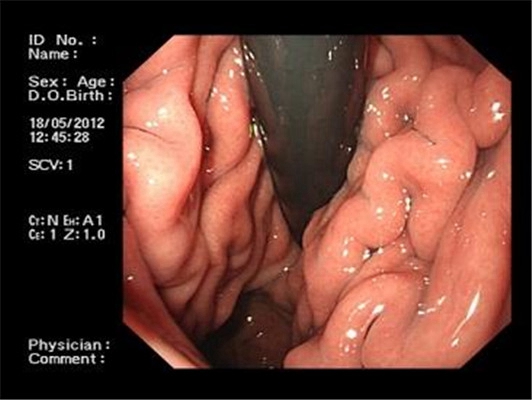

食道炎圖片